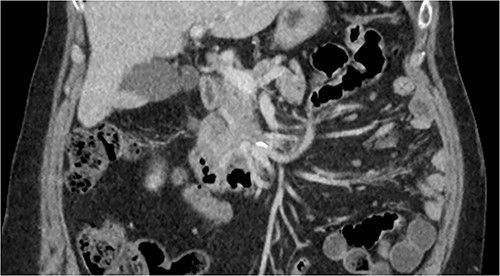

A multiphase CT of the pancreas had unexpected findings. There were no pancreatic masses on the arterial and portal phase study, and no paraaortic or mesenteric lymphadenopathy. The abnormal calcification seen on the previous study corresponded to a dilated vessel along the superior margin of the pancreatic body. This dilated vessel was an abnormal communication between a tortuous ecstatic gastroduodenal artery and the first branch of the SMA, a Buhler’s arc communication. The celiac axis origin was narrowed >90%. No other suspicious solid organ mass lesion was identified. Soft tissues were unremarkable (Figs 5–8).

Multiphase CT pancreas, coronal view: the gastroduodenal artery, off the common hepatic, communicating with the first branch of the SMA.

Multiphase CT pancreas, sagittal view: abnormal communication between the CA and the SMA. The celiac axis is markedly narrowed, >90%.